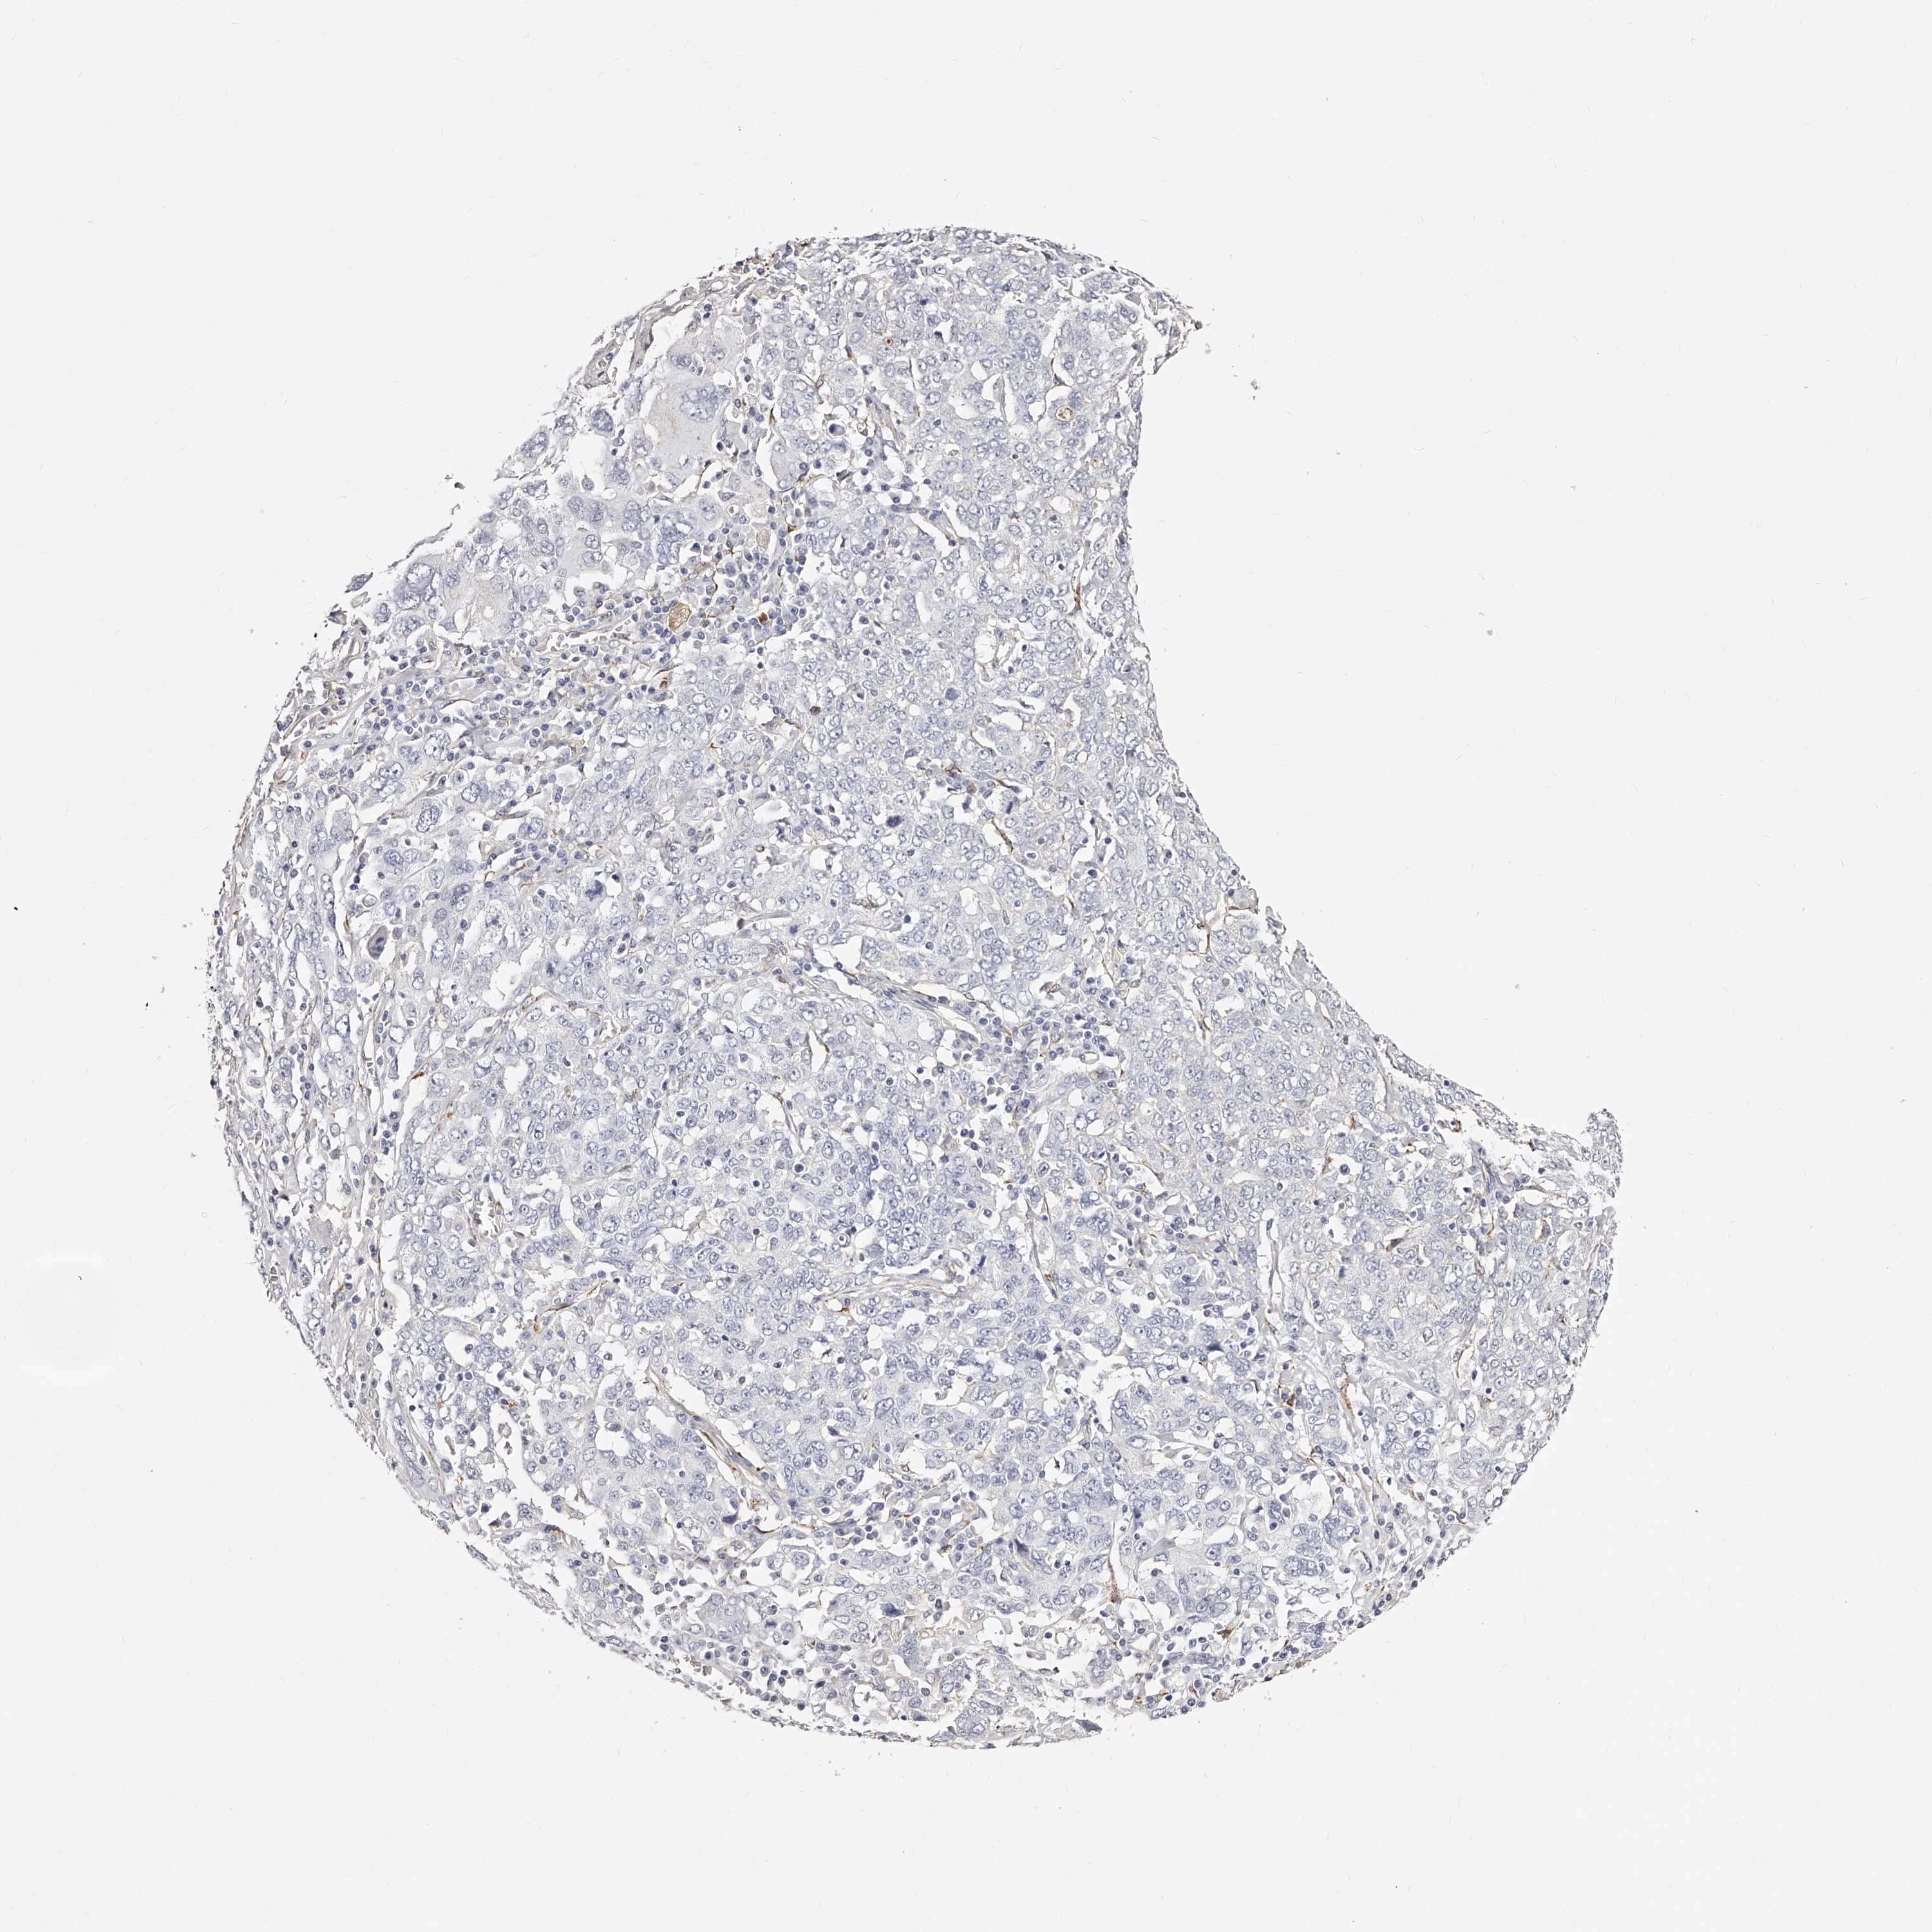

OVARIAN CANCER - Protein expressioni

A mouse-over function shows sample information and annotation data. Click on an image to view it in a full screen mode. Samples can be filtered based on level of antibody staining by selecting one or several of the following categories: high, medium, low and not detected. The assay and annotation is described here.

Note that samples used for immunohistochemistry by the Human Protein Atlas do not correspond to samples in the TCGA dataset.

Antibody stainingi

Antibody staining in the annotated cell types in the current human tissue is reported as not detected, low, medium, or high, based on conventional immunohistochemistry profiling in selected tissues. This score is based on the combination of the staining intensity and fraction of stained cells.

Each image is clickable and will lead to virtual microscopy that enables deeper exploration of all samples and also displays staining intensity scores, fraction scores and subcellular localization as well as patient and tissue information for each sample.

Antibody HPA028900

Antibody CAB002508

Cystadenocarcinoma, serous, NOS

Carcinoma, endometroid

Cystadenocarcinoma, mucinous, NOS

Carcinoma, NOS